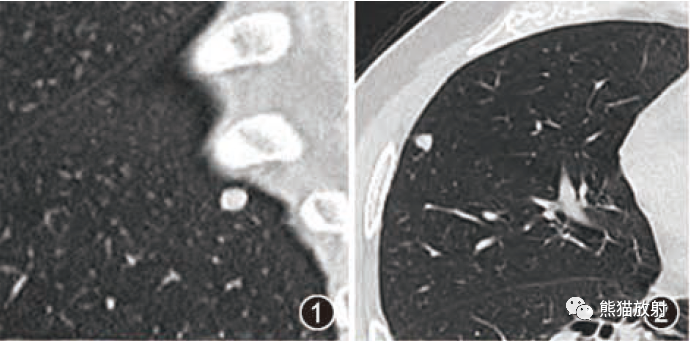

纵隔大细胞神经内分泌癌1例CT影像

纵隔大细胞神经内分泌癌1例CT影像  张力性纵隔气肿影像表现及严重度分级

张力性纵隔气肿影像表现及严重度分级  迅速增大的肺部结节,首先考虑良性,确诊需要肺穿